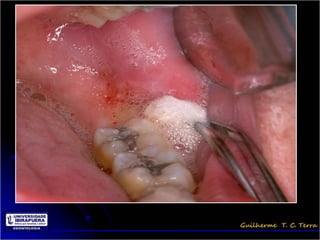

Pericoronarite

• Infecção dos tecidos moles (Opérculo)

que recobrem a coroa de um dente

incluso

• A dificuldade de higienização sob o

opérculo

Tratamento da Pericoronarite

• Limpeza mecânica do opérculo através de

irrigação com soro ou água oxigenada 10 vol

• Higienização dolocal pelo paciente e irrigações

com água oxigenada 10 vol

• Antibioticoterapia

• Exodontia